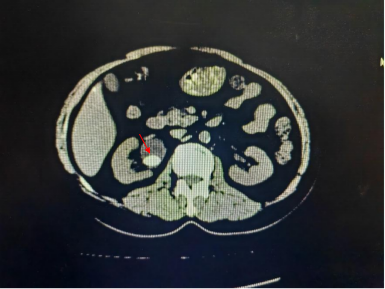

患者入院行腹部CT检查。发现右肾结石,大小约2.0cm